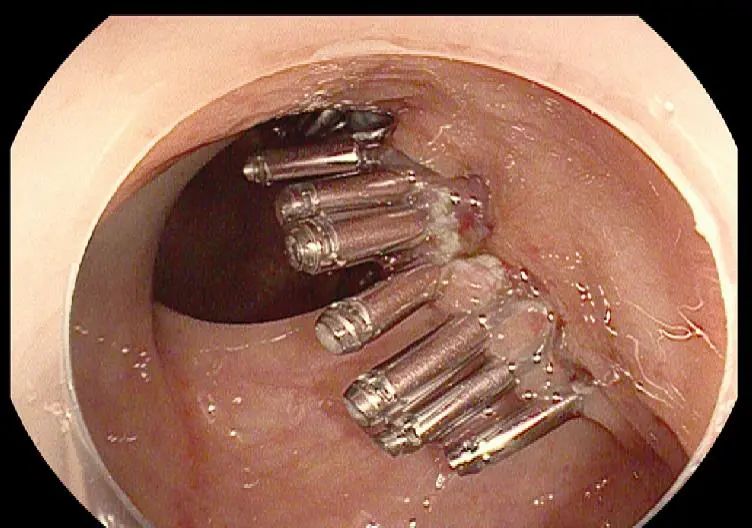

近日,一位患者来我院行胃肠镜普查,在肠镜检查中发现直肠有一处粘膜隆起型病变,椭圆形,大小约10mm*12mm,怀疑直肠早癌可能性大,但无法确切判断浸润深度,于是内镜医师用上了“新式武器”-小探头超声内镜,进一步为患者做了超声内镜检查,发现病变起源于粘膜层,粘膜下层连续完整,初步考虑可行微创治疗切除病变组织,随即于内镜下行直肠粘膜剥离术(ESD),完整切除病变,组织夹夹闭创面,创面完好无出血,随后病理结果证实了术前诊断,因为及时进行了超声内镜检查,能够指导医师尽快评估病情,最短时间内为患者提供了最适宜的诊疗方案,获得了患者及家属的赞誉。

我院使用的小探头超声内镜是一种将内镜与超声相结合的综合技术,是通过内镜(胃镜、结肠镜)导入微型超声探头,在内镜直视下对消化道(食管、胃、结肠)管壁进行超声扫描的方法。超声内镜作为内镜医生的“雷达”,它不仅具有普通内镜的功能,还可同时对食管壁和胃肠壁等组织进行超声扫描,能够清晰的探测和分辨出胃肠壁的各层次结构,并对病变进行初步判断。